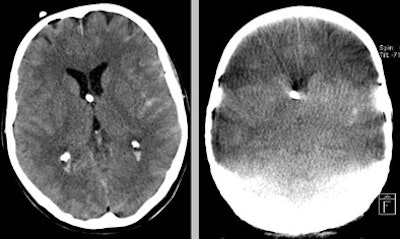

| A supratentorial subarachnoid hemorrhage (SAH) is missed at flat-panel CT (right). All images courtesy of Dr. Stephan Celedin. |

The infratentorial region showed total agreement in 50% of the cases. For detecting infratentorial SAH of any size, there were 13 false negatives, a sensitivity of 44% (23% to 66% CI), and a specificity of 86% (42% to 100% CI). For detecting infratentorial SAH 5 mm and larger, there were nine false negatives and two false positives, with sensitivity of 48% (23% to 72% CI) and specificity of 85% (55% to 98% CI).

Side-by-side reading improved agreement to 66% with a sensitivity of 61% and specificity of 100%. The temporal horn was not discernable with flat-panel CT in 7% of patients; the 4th ventricle could not be seen in half of the cases. Two intracerebral hemorrhages (50%) were missed at flat-panel CT, and two others were measured identically compared to cranial CT. In side-by-side viewing, a supratentorial intracerebral hemorrhage was detected.